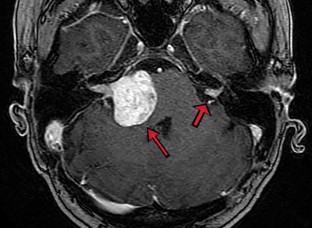

Abb. 1

• Schwannom

• Neurofibromatose 2

• Schwannoma

• Neurofibromatosis 2